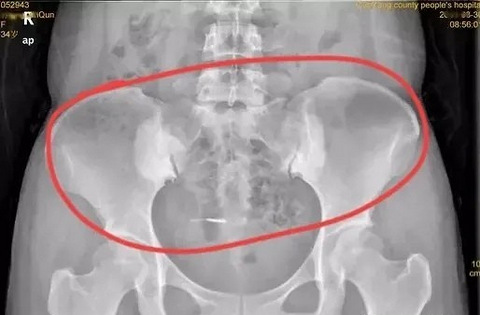

普通妇科门诊一天,经常发生的一幕

转自北京高级职称医生一枚 今天顺序两个一脸懵懂,一脸青涩,眼神清澈,貌似学生的女孩子走进我的诊室,在我眼里她真还是孩子,她上来就说“大夫,我怀孕了,我想做流产”。 我看了眼计算机上她们的资料,20岁,19岁,都是花一样的年级。 查了超声如下: